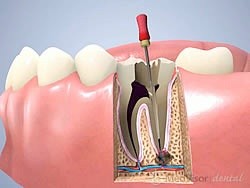

再感染を防ぎ天然歯を守る歯内療法

歯内療法は地道な工程を積み重ねる治療ですが、天然歯を守るために欠かせない役割を担っています

歯内療法は、歯の内部にある壊死した神経や腐敗した感染性物質を清掃し、根尖部に生じた病変の改善を図る治療です。

むし歯が進行して歯髄にまで感染が及んだ場合や、根の先に炎症が広がった場合に行われます。

歯科医院で実施される処置の中でも頻度が高く、歯を抜かずに残すための重要な治療の一つとされています。

感染源を的確に取り除き、歯の内部環境を整えることで、症状の改善と機能の維持を目指します。

処置は非常に細かく繊細であり、根管内の複雑な構造を把握しながら丁寧に進める必要があります。

そのため、一定の処置時間と複数回の通院を要することがあります。

治療効果の判定にも時間がかかる場合があり、経過観察を行いながら慎重に状態を確認します。

特に治療中に唾液が侵入すると感染の再発につながる可能性があるため、管理を徹底しながら進めることが重要です。

丁寧な清掃と確実な封鎖を行うことで再感染のリスクを抑え、長期的な歯の保存につなげていきます。

歯内療法は地道な工程を積み重ねる治療ですが、天然歯を守るために欠かせない役割を担っています。